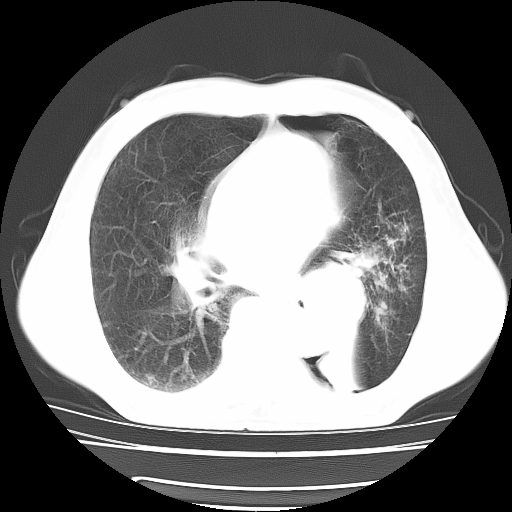

男,71岁,咳嗽,气喘10年,再发并咯血.胸片见气胸

考虑  左肺中心型肺癌伴阻塞性肺炎,肺不张,纵膈淋巴结肿大。慢支炎,肺气肿,左侧气胸肺压缩5%

左侧中央型肺癌伴纵膈淋巴结转移。

左肺中心型肺癌伴阻塞性肺炎,肺不张,纵膈淋巴结肿大

1)考虑左肺中心型肺癌伴阻塞性肺炎、左肺下叶肺不张、左侧肺气肿,纵膈淋巴结转移。2)左侧气胸(肺组织压缩约5%)。

左肺中心型肺癌伴阻塞性肺不张、肺气肿 。

1)考虑左肺中心型肺癌伴阻塞性肺炎、左肺下叶肺不张、左侧肺气肿,纵膈淋巴结转移。2)左侧气胸。